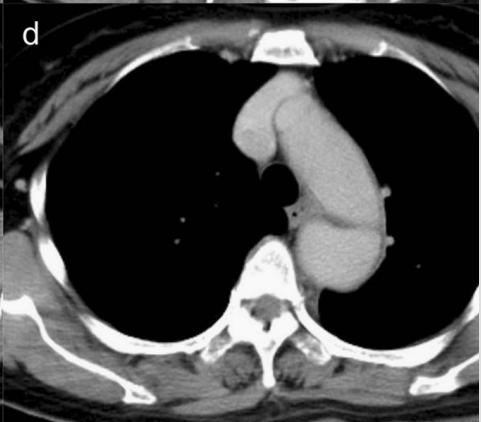

病例9

下面这个CT平扫,似乎有大问题!

图22

什么问题?似乎这里有大问题!

图23

同学,你眼神太好使了!

很可惜,这个不是问题,很多CT平扫都有这种线样阴影!

做个增强CT一看,哇,同学,你不光眼神好,运气也不是一般的好!

图24